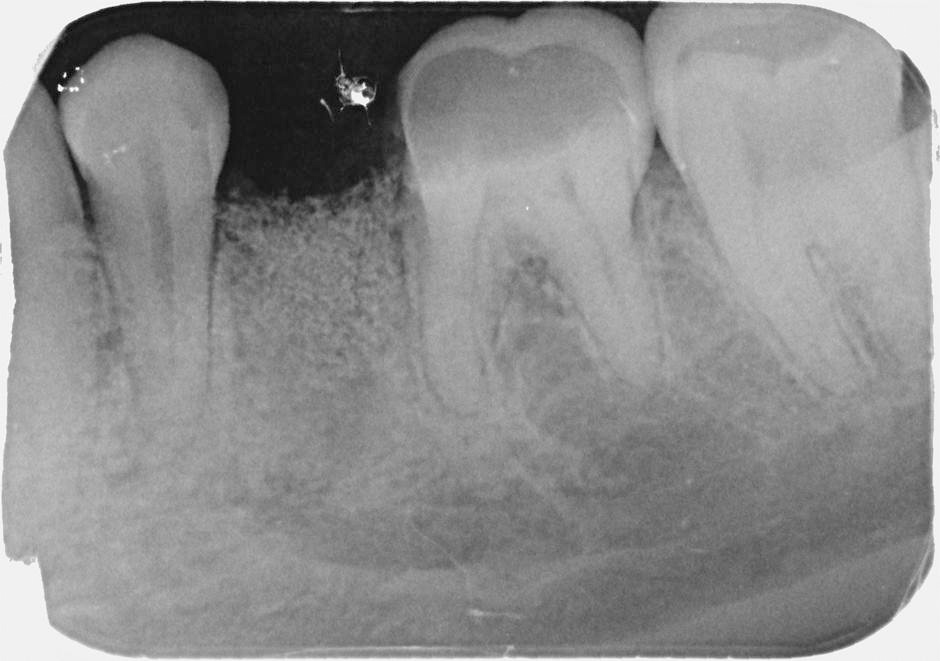

Při ztrátě molárů a premolárů v horní čelisti a jejich náhradě implantáty se často setkáváme s nedostatečnou

vertikální nabídkou kosti pod čelistní dutinou, často doprovázenou i nedostatečnou horizontální nabídkou a sníženou kvalitou kosti (v oblasti 2. premoláru v 50%, v oblasti moláru až v 80% případů nedostatečná kostní nabídka)

Jedná se o vyzvednutí membrány, která čelistní dutinu vystýlá, pod vyzvednutou membránou vznikne kapsa, kam se umístí augmentační materiál, do kterého se zavedou implantáty.

Vhojení implantátů se při této operaci prodlužuje na 6-12 měsíců.